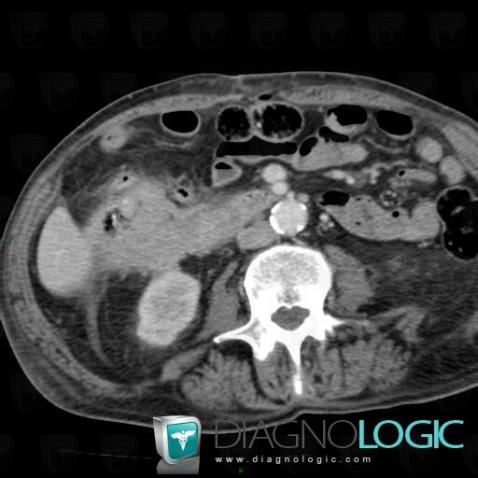

Colon cancer, Colon, CT

Here is the specific information in the key image above:

- Diagnosis Colon cancer, Location(s) Colon, with gamuts Thickening of colon wall, Colonic mass or filling defect